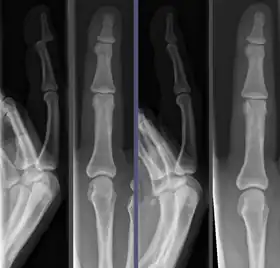

![]() Joint dislocation in the DIP of the third finger before (left images) and after (right images) reduction. | |

Once the fragments are reduced, the reduction is maintained by application of casts, traction, or held by plates, screws, or other implants, which may in turn be external or internal. It is very important to verify the accuracy of reduction by clinical tests and X-ray, especially in the case of joint dislocations.